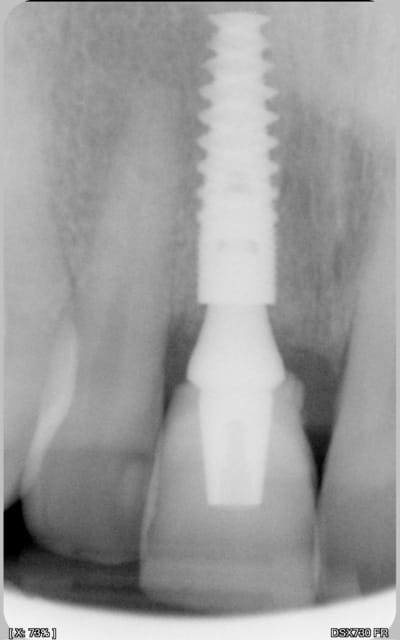

petite question: sur la photo 15, c'est la prothèse d'usage je pense, il me semble que le hiatus prothèse / pilier est important?

A pxav

Il semble effectivement qu'il y ai un hiatus important.

Je n'ai pas contrôlé l'ajustage sur le modèle car ayant travaillé avec une réplique de pilier et une chape calcinable je pensais pas qu'il puisse y avoir de défaut. A l'essayage clinique, je n'ai rien relevé à la sonde (comme quoi une sonde...) et la coiffe paraissait être à fond (occlusion et bord libre). Seule la radio de contrôle m'a révélé le problème. Comme la coiffe était déjà scellée, j'ai choisi de ne pas démonter. A surveiller....